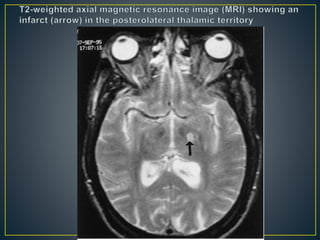

• Infarcts in this thalamic territory are due to occlusion of

the geniculothalamic (thalamogeniculate, posterolateral)

artery, a branch of the posterior cerebral artery.

• Thalamic structures involved by the infarct are the

primary sensory thalamic nuclei, which include the

ventral posterior lateral, ventral posterior medial, medial

geniculate, pulvinar, and centromedian nuclei

• The clinical hallmark of posterolateral thalamic territory

infarcts is a pansensory loss contralateral to the lesion,

paresthesia, and thalamic pain.

• In addition, one or more of the following may occur:

transient hemiparesis, homonymous hemianopsia,

hemiataxia, tremor, choreiform movements, and spatial

neglect, all contralateral to the lesion in the thalamus.

• An athetoid posture of the contralateral hand (thalamic

hand) may appear 2 or more weeks following lesions in

this territory.

• The hand is flexed and pronated at the wrist and

metacarpo-phalangeal joints and extended at the

interphalangeal joints. The fingers may be abducted. The

thumb is either abducted or pushed against the palm.

• The conglomerate of signs and symptoms associated

with posterolateral thalamic territory infarcts comprises

the thalamic syndrome of Dejerine and Roussy.

• In this syndrome, severe, persistent, paroxysmal, and

often intolerable pain (thalamic pain) resistant to

analgesic medications occurs at the time of injury or

following a period of transient hemiparesis, hemiataxia,

choreiform movements, and hemisensory loss

• Cutaneous stimuli trigger paroxysmal exacerbations of

the pain that outlast the stimulus. Because the perception

of “epicritic” pain (from a pinprick) is reduced on the

painful areas, this symptom is known as anesthesia

dolorosa, or painful anesthesia